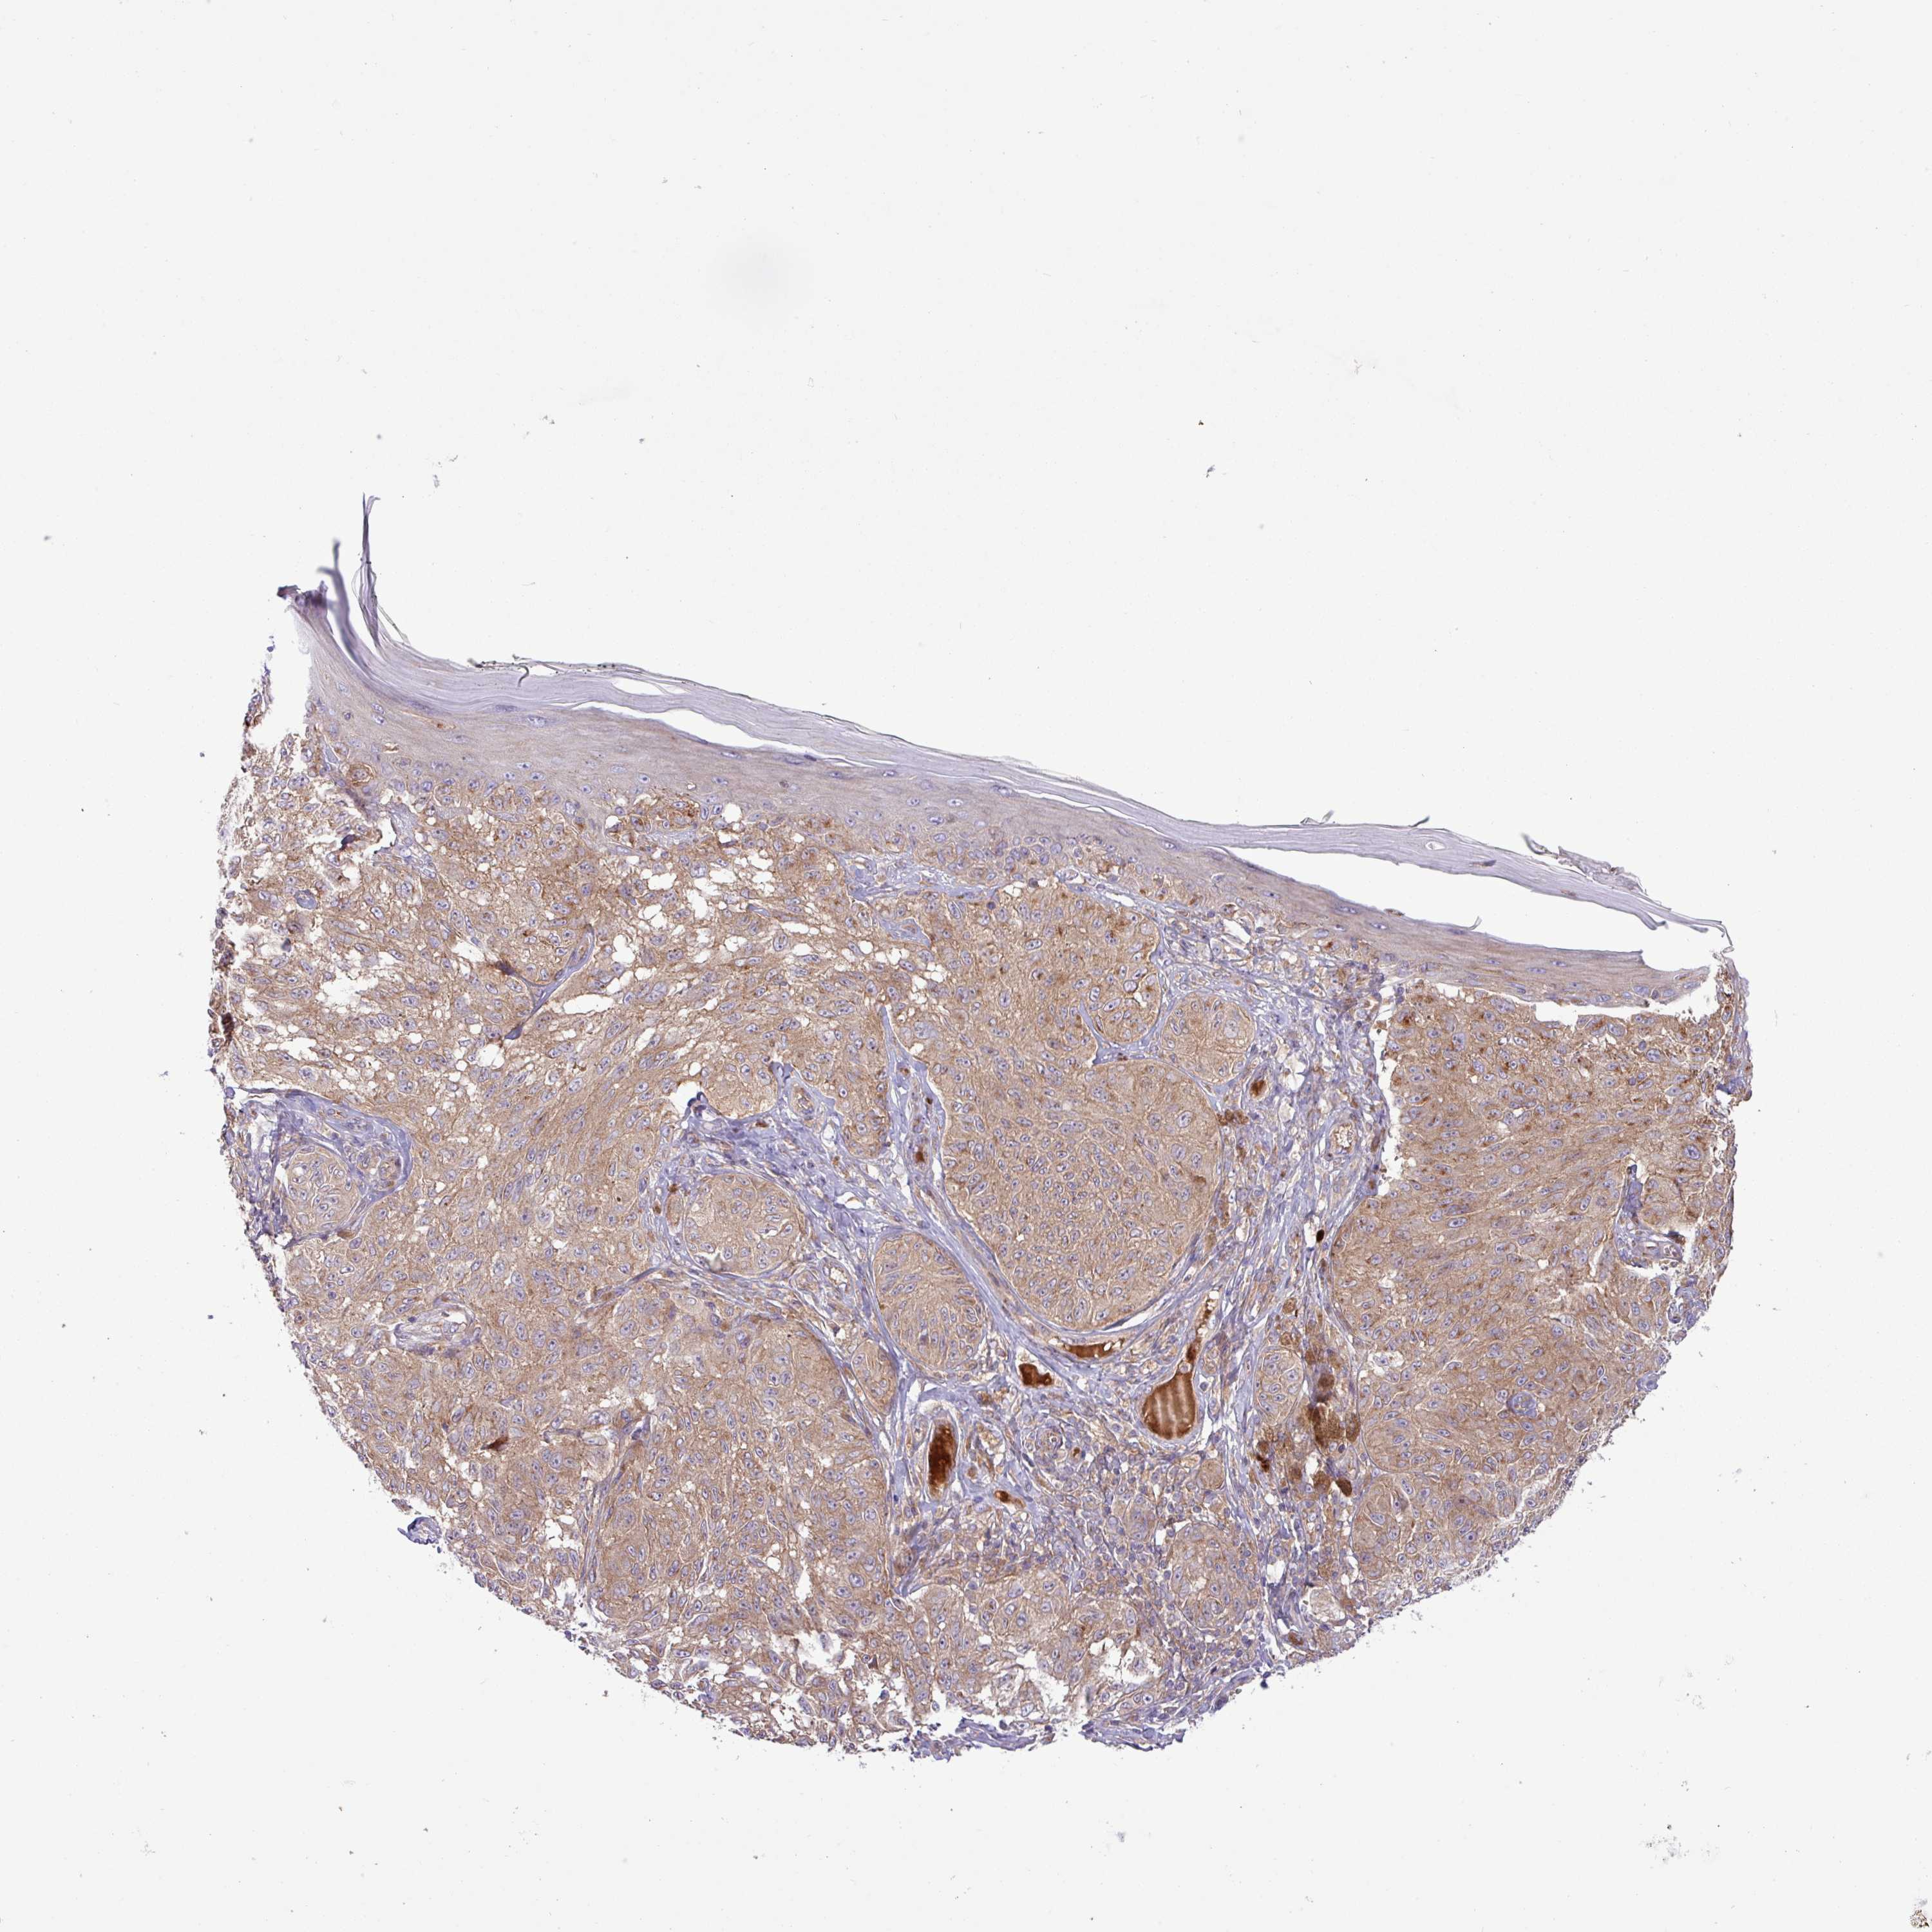

MELANOMA - Protein expressioni

A mouse-over function shows sample information and annotation data. Click on an image to view it in a full screen mode. Samples can be filtered based on level of antibody staining by selecting one or several of the following categories: high, medium, low and not detected. The assay and annotation is described here.

Note that samples used for immunohistochemistry by the Human Protein Atlas do not correspond to samples in the TCGA dataset.

Antibody stainingi

Antibody staining in the annotated cell types in the current human tissue is reported as not detected, low, medium, or high, based on conventional immunohistochemistry profiling in selected tissues. This score is based on the combination of the staining intensity and fraction of stained cells.

Each image is clickable and will lead to virtual microscopy that enables deeper exploration of all samples and also displays staining intensity scores, fraction scores and subcellular localization as well as patient and tissue information for each sample.

Antibody HPA051077

Staining

High

Medium

Low

Not detected

Intensity

Strong

Moderate

Weak

Negative

Quantity

>75%

75%-25%

<25%

None

Location

Nuclear

Cytoplasmic/membranous

Cytoplasmic/membranous,nuclear

Malignant melanoma, NOS

Malignant melanoma, Metastatic site